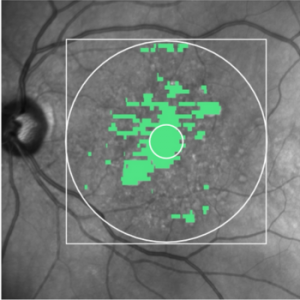

ki-diagnosesoftware